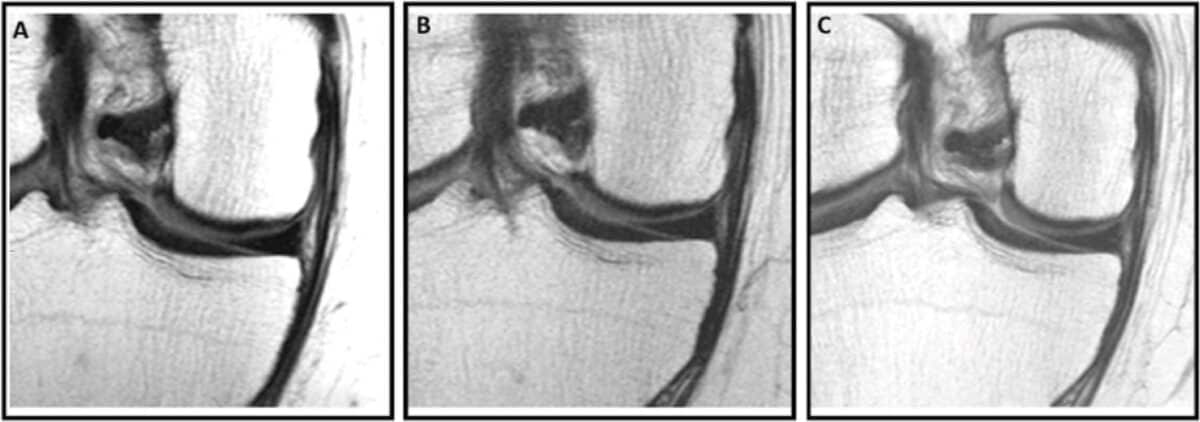

What set this study apart was its use of detailed MRI scans to assess joint health. Researchers evaluated images from two years before the injection, at the time of injection, and again two years afterward using the Whole-Organ MRI Score (WORMS). This scoring system provides a comprehensive assessment of cartilage, bone marrow, meniscus, ligaments, and joint effusion.

MRI images helped visualize the contrast. In a 58-year-old woman who received a steroid injection, follow-up scans showed new full-thickness cartilage lesions and bone marrow damage. In a 57-year-old man who received hyaluronic acid, the same cartilage remained intact and unchanged over four years.

Researchers conducted a secondary analysis of data from the Osteoarthritis Initiative, following 210 participants (mean age 64 years, 60% female) over multiple years. They used detailed 3-T MRI scans taken at three time points: two years before injection (T-2), at the time of injection (T0), and two years after injection (T+2). The study compared three groups—those who received corticosteroid injections (44 people), hyaluronic acid injections (26 people), and propensity-score matched controls who received no injections (140 people). Joint health was measured using the comprehensive Whole-Organ MRI Score (WORMS) system rather than simple X-rays. Only participants with a single injection during the study period were included.

Corticosteroid injections were associated with greater WORMS progression compared to both controls (mean difference, 0.39; 95% CI: 0.05, 0.75; P = .02) and hyaluronic acid injections (0.42; 95% CI: 0.01, 0.84; P = .04) over the two-year follow-up period. Hyaluronic acid injections showed decreased progression compared to the pre-injection period (mean difference, −0.42; 95% CI: −1.34, −0.28; P = .003). Both injection types delivered pain relief, with corticosteroid injections reducing WOMAC pain scores by 5.20 points (P = .001) and hyaluronic acid by 2.15 points (P = .04). The differences were particularly notable in cartilage deterioration.